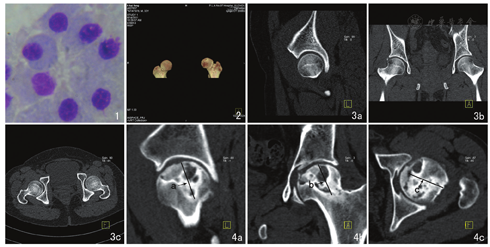

经双侧髂前上棘或髂后上棘分别抽取患者骨髓40 ml,肝素抗凝,用人间充质干细胞分离液分离单个核细胞,吸取单个核细胞,体外增生培养诱导。收集增生培养诱导14 d的MSC(图1)制备成3~5 ml细胞悬液供患者治疗使用,MSC数量约为1×107~1.5×107个。

31例患者共36髋ANFH,I期8髋,占22.22%;II期22髋,占61.11%(其中IIa期5例、IIb期6例、IIc期11例);III期6髋,占16.67%。I期:股骨头坏死区骨小梁增粗、变形,轻度骨质疏松,呈"星芒状"改变。II期:股骨头坏死区骨质疏松,皮质下可见小囊变,骨小梁"星芒状"结构消失,内有点片状密度增高影;I~II期MPVR显示整个股骨头解剖形态正常(图2),MPR显示关节间隙清楚(图3)。III期:MPR示股骨头关节面下有大小不等的囊状低密度区,其间散在分布斑片状骨质硬化影,出现"新月"征象和轻度碎裂表现(图4)。

将坏死区设想为近似球柱体,在MPR图像上,分别测量矢状面、冠状面及横断面上坏死区的最大直径,用a、b、c表示(图4),V表示坏死区的体积,V=4π/3×a/2×b/2×c/2。I期股骨头坏死区的体积为(1218.97±449.93)mm3,II期股骨头坏死区的体积为(3671.19±1316.83)mm3,III期股骨头坏死区体积为(7874.18±2381.22)mm3。